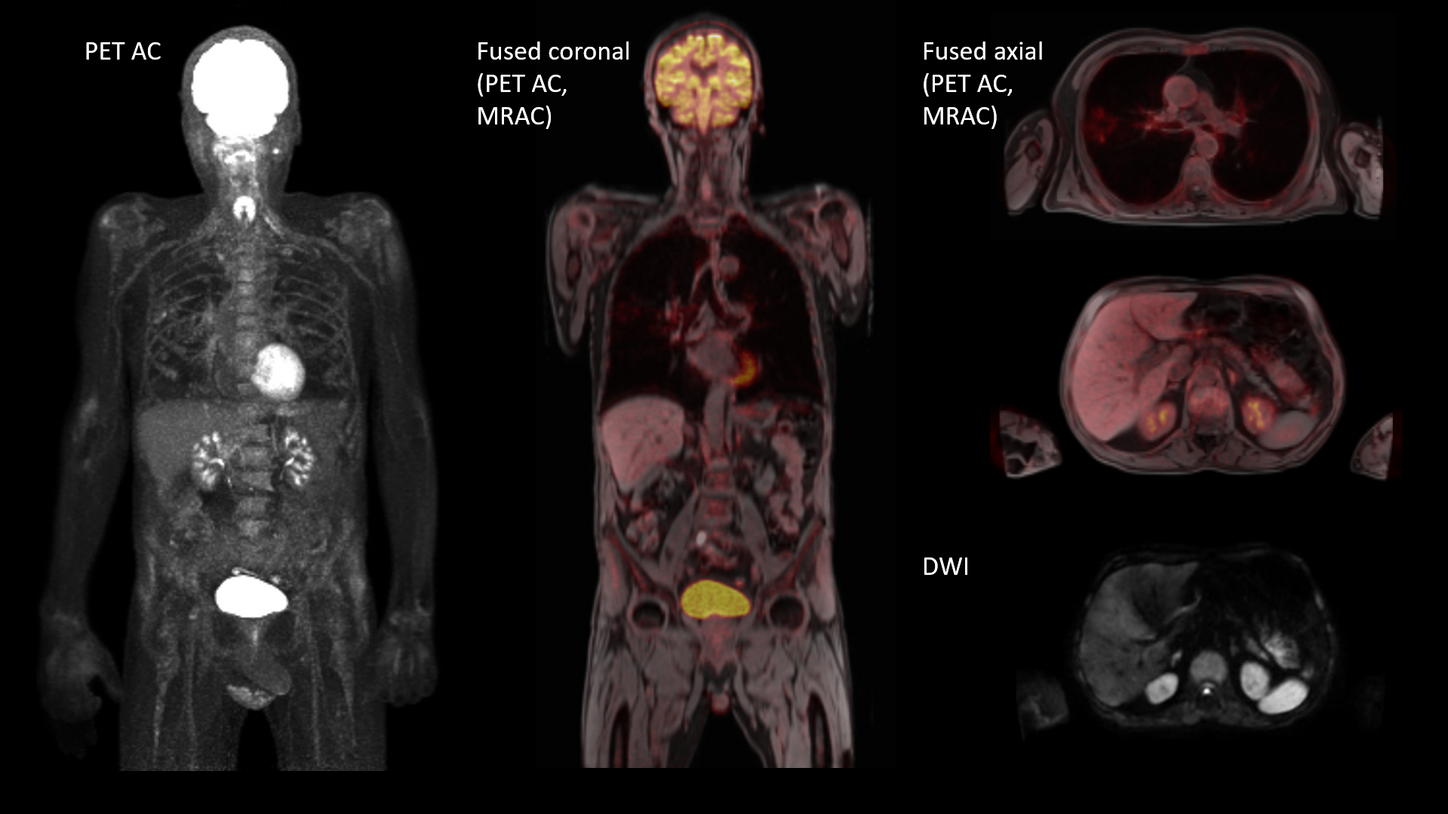

BIOGRAPH One is designed to excel in PET/MR precision to support confident diagnostic decisions. Featuring the Optiso UDR Pro detector with the largest 35 cm axial FOV2 in PET/MR, it is designed to enable comprehensive capture with excellent sensitivity and ultra-fast TOF3 in real time – delivering clear, detailed images.

Planned with Deep Resolve for accelerated acquisition and improved resolution in 2D and 3D applications4, BIOGRAPH One has the potential to make PET/MR exams faster than ever before. Designed with a powerful 3T magnet at its heart, BIOGRAPH One will deliver unparalleled performance with outstanding homogeneity, a large 55 x 55 x 50 cm³ field of view and robust gradient power.